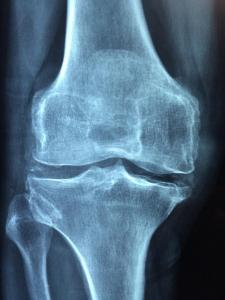

FamilyCare Medical Group offers bone density testing (dexascan), a test that measures bone density, a factor in osteoporosis. Osteoporosis is an illness that makes people prone to breaking bones. It is common in post-menopausal women and in some other medical conditions. A bone density measurement is similar to an x-ray and takes from 5-20 minutes. It is simple, safe, painless, and non-invasive. This measurement helps your physician to determine if you need to take certain steps to protect your bone health.